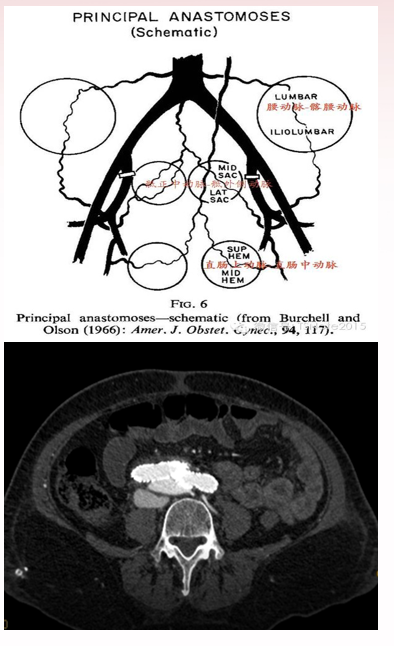

★ EVAR手术栓塞或覆盖骼内动脉后盆腔血流动力学影响

回顾该EVAR手术栓塞或覆盖髂内动脉后,对盆腔血流动力学影响显著。虽然髂内动脉结扎及腔内栓塞在多种治疗中常用,如作为妇科,肿瘤,开放或血管介入治疗常见手术方式,但大量文献提示,EVAR手术阻断髂内动脉血流,虽致命的并发症率不高,却易引发盆腔多种并发症。对于大多数腹主动脉瘤(AAA)患者,其盆腔脏器血液供应本就处于边缘状态甚至恶化状态,髂内动脉栓塞可能诱发或加重盆腔缺血,使隐性缺血转为显性缺血。

2017年Kontopodis等[44]综述了8个研究报告,284例EVAR中采用髂动脉延长支直接遮盖髂内动脉开口,255例先栓塞髂内动脉再延长覆盖开口。两者盆腔缺血并发症率分别为6%和29%,差异显著。而两组间2型内漏差别不大。本例实施栓塞者术前有出于担心动静脉内漏以及2型内漏的考虑,术后发生臀肌缺血风险升高。

★ AAA合并ACF动脉供血阻断的后果?

静脉瘘封堵或栓塞后,动脉端压力下降,而下腔静脉处于负压状态,会抽吸动脉远端分支血液,会在短时间内引发严重的臀肌缺血。

上海九院的范新东教授团队在ACF治疗方面提出了独特见解。认为在处理ACF时,不应率先封堵动脉端,而应关注静脉端的处理。传统的单纯封堵动脉供血,可能会使静脉瘘槽依然存在,由于静脉的负压特性,会使原本不供应病变周围的动脉分支及交通支全部开放,形成“盗血效应”,进而引发更严重的后果。基于此,提出应进行双向栓塞或阻断动静脉瘘的观点。这种方法旨在更全面地控制动静脉之间的异常血流,减少并发症的发生风险。